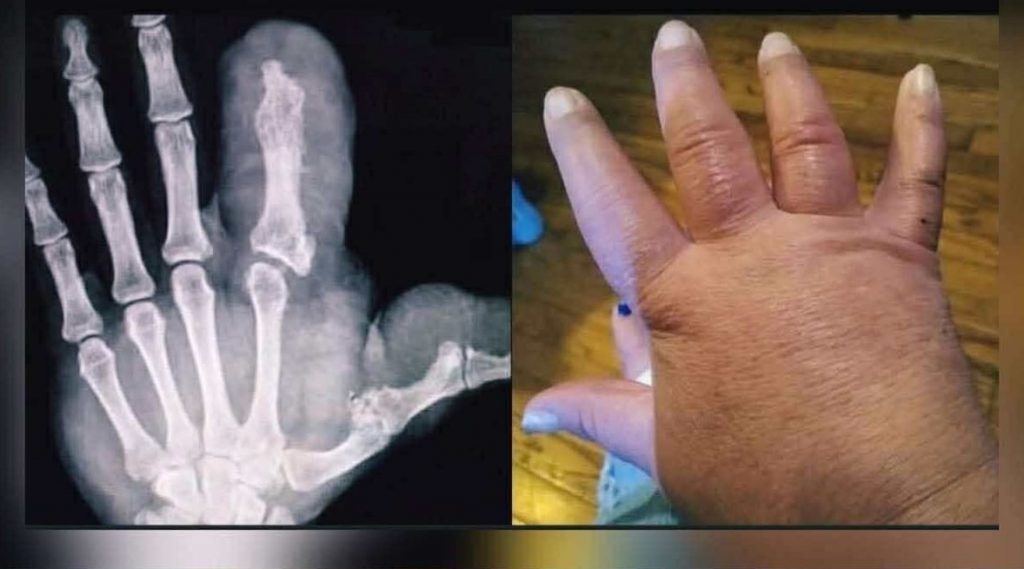

Od narození jí palec rostl rychleji než zbytek ruky. Zpočátku se to zdálo triviální – dětská vrtoch, o které se diskutovalo s úsměvem. Ale rok co rok se kůže napínala, nehet se stal jako malá mušle a ruka ztrácela svůj známý tvar. Lékaři tomu říkali slovo, které znělo téměř cize – makrodaktylie. Vysvětlovalo to všechno a zároveň nic.